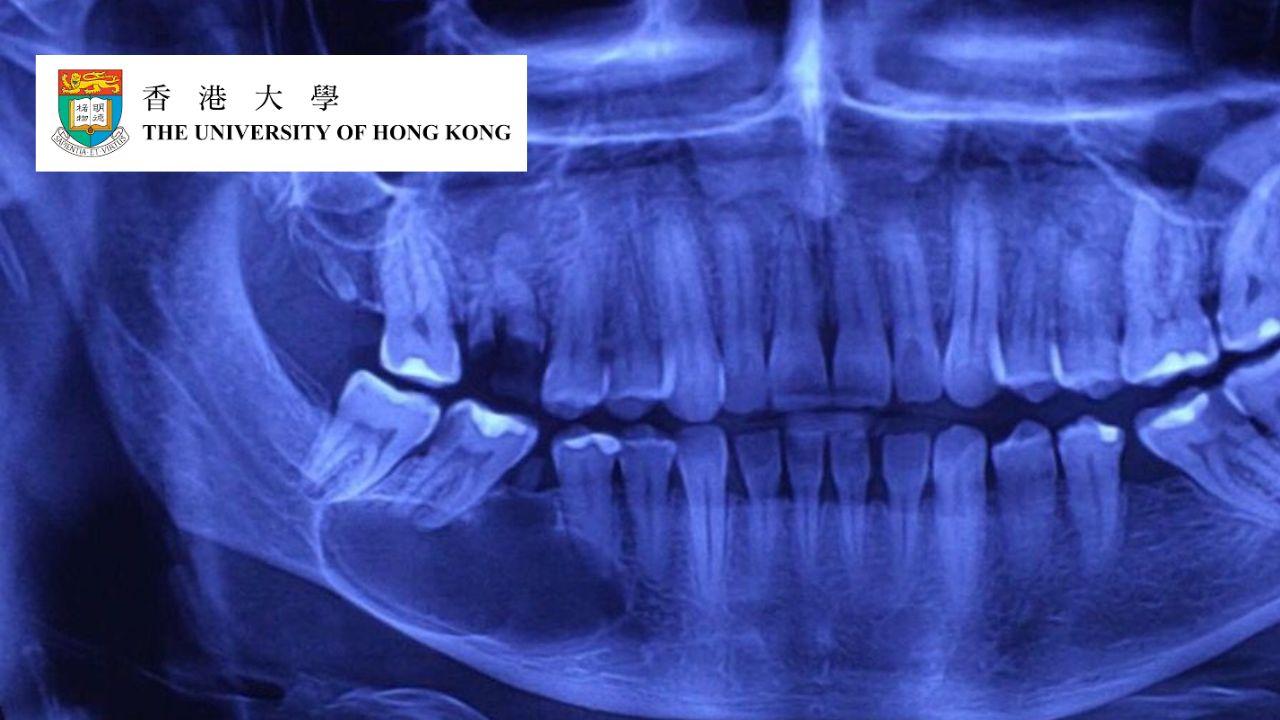

Master dental imaging techniques with 2D/3D modalities, radiation protection, and diagnostic skills for dental professionals.

Explore the benefits and limitations of 2D/3D imaging in dental medicine

Understand anatomy and pathology in radiographic images

Master image interpretation and diagnostic reporting